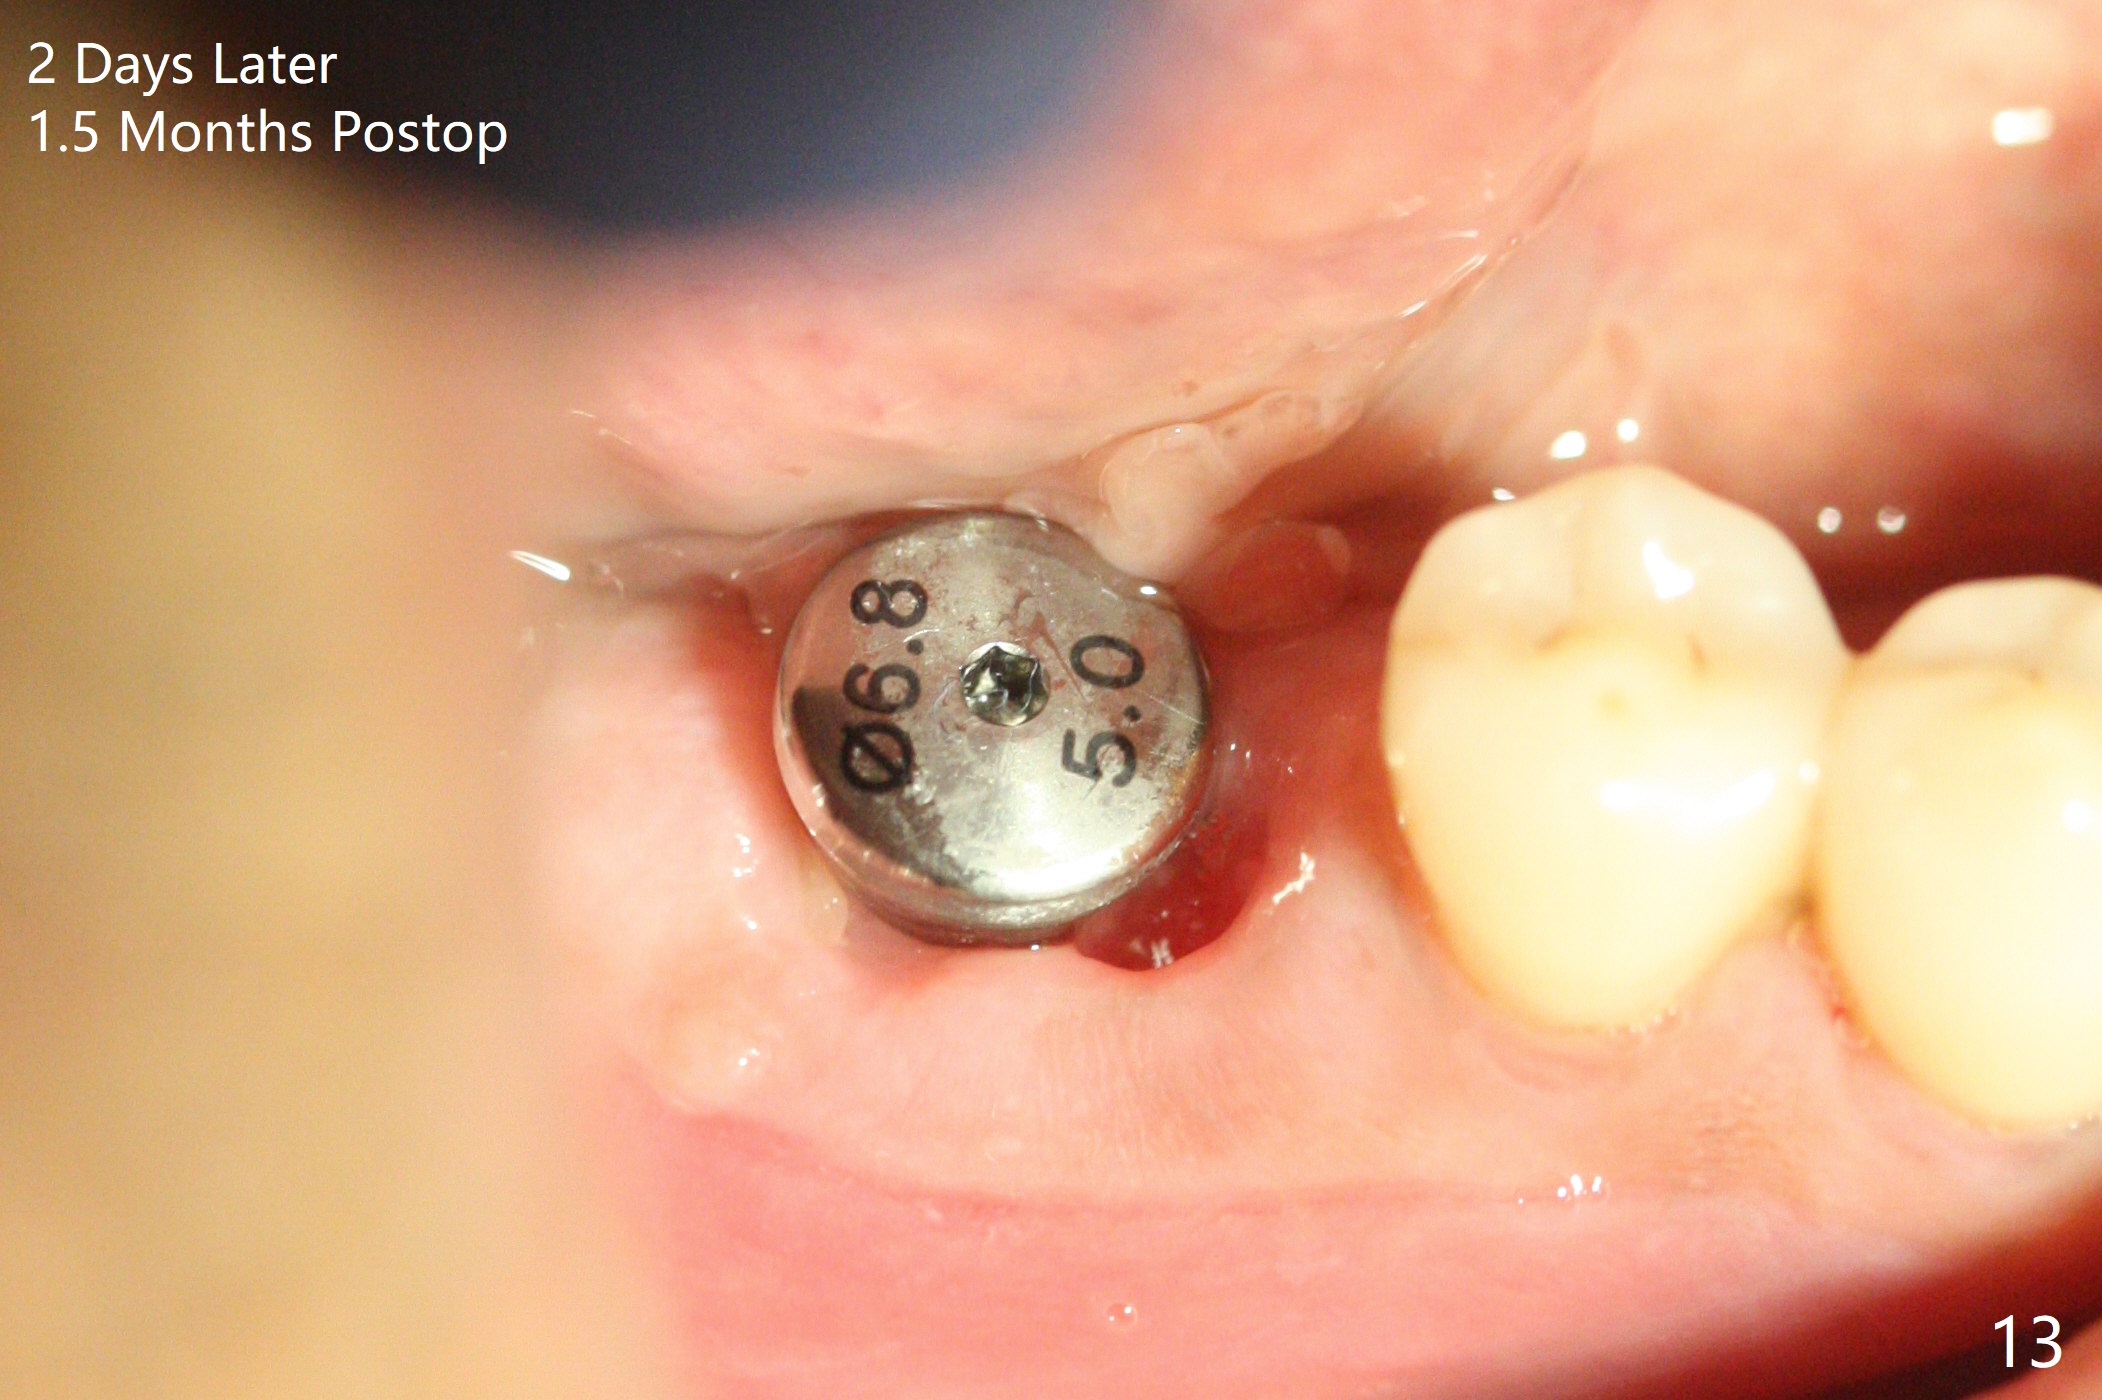

Abutment vs. Definitive One

After extraction of the tooth #30 with lingual subgingival fracture (Fig.1), the septum is fairly large (Fig.2 S). A bony vertical anchor pin (Fig.3 *) is inserted in the septum following pointed drill to to stabilize the guide during osteotomy and implant placement of #31. When the latter is finished, a fixture anchor pin is used at #31 as planned. A healing abutment is placed at #31 because of supraeruption of the tooth #2 (Fig.4,5), while a cementation abutment is placed at #30 (Fig.5) with autogenous bone (from drills) and allograft placed around it (*, Fig.6). Finally an immediate nonfunctional provisional is fabricated to keep the bone graft in place (Fig.7 P). The bone graft remains in place gel-like nearly 1 month postop (Fig.8). CBCT axial section shows that there is not enough space for mini implant placement at the tooth #2 (Fig.9). Restoration-induced intrusion will be conducted using the implants at #30 and 31 three-4 months postop. The buccal gingiva (Fig.10 *) is lingual to the provisional (P) nearly 1.5 months postop. When the provisional is removed, it appears that the mesiobuccal bone graft has lost (Fig.11). Two days later, the cementation abutment is loose and removed; the gingival cuff looks healthy (Fig.12). A 6.8x5 mm healing abutment is placed (Fig.13). In 2.5 to 3 months, abutments will be placed at #30 and 31. Splinted provisional will be fabricated over supraocclusion to intrude the tooth #2 with a stop on the left side. Surprisingly the patient agrees to intrude the tooth #2 with 2 mini implants 5.5 months postop (Fig.14,15). However, the miniimplants dislodged. Due to coronavirus, the implants are restored with heavy abutment and opposing tooth trimming 1 year 9 months postop (Fig.16). Magicore should have been placed instead.